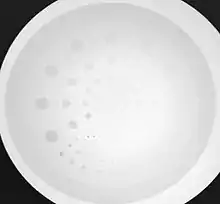

- Contrast-detail evaluation combines physical indices of image quality with observer detection ability. Contrast-detail phantoms contain test objects of different sizes and subject contrast mounted on a plastic plate that is radiographed under specific exposure conditions - see Figure 6.20. Contrast-detail plots are derived on the basis of the borderline visibility of test objects in the image. A disadvantage of this approach however is the introduction of bias as a result of the observer's prior knowledge of the size, shape and location of the low-contrast objects. The link between this type of evaluation and clinical imaging performance is therefore difficult to establish.